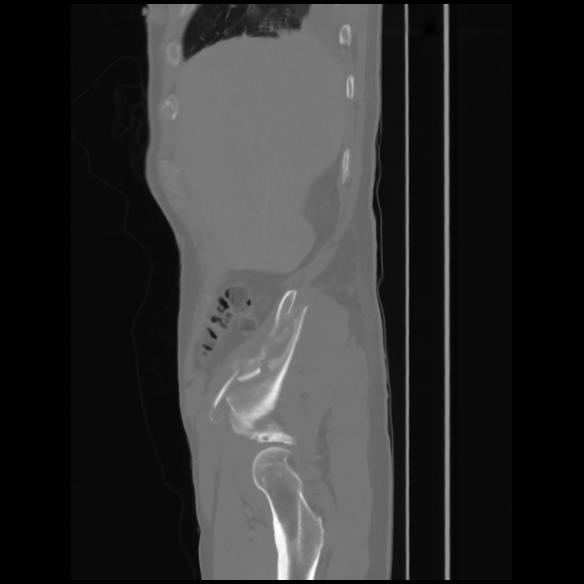

7 CUERPO,CE,Sagittal,3.000,CUERPO,Sagittal,